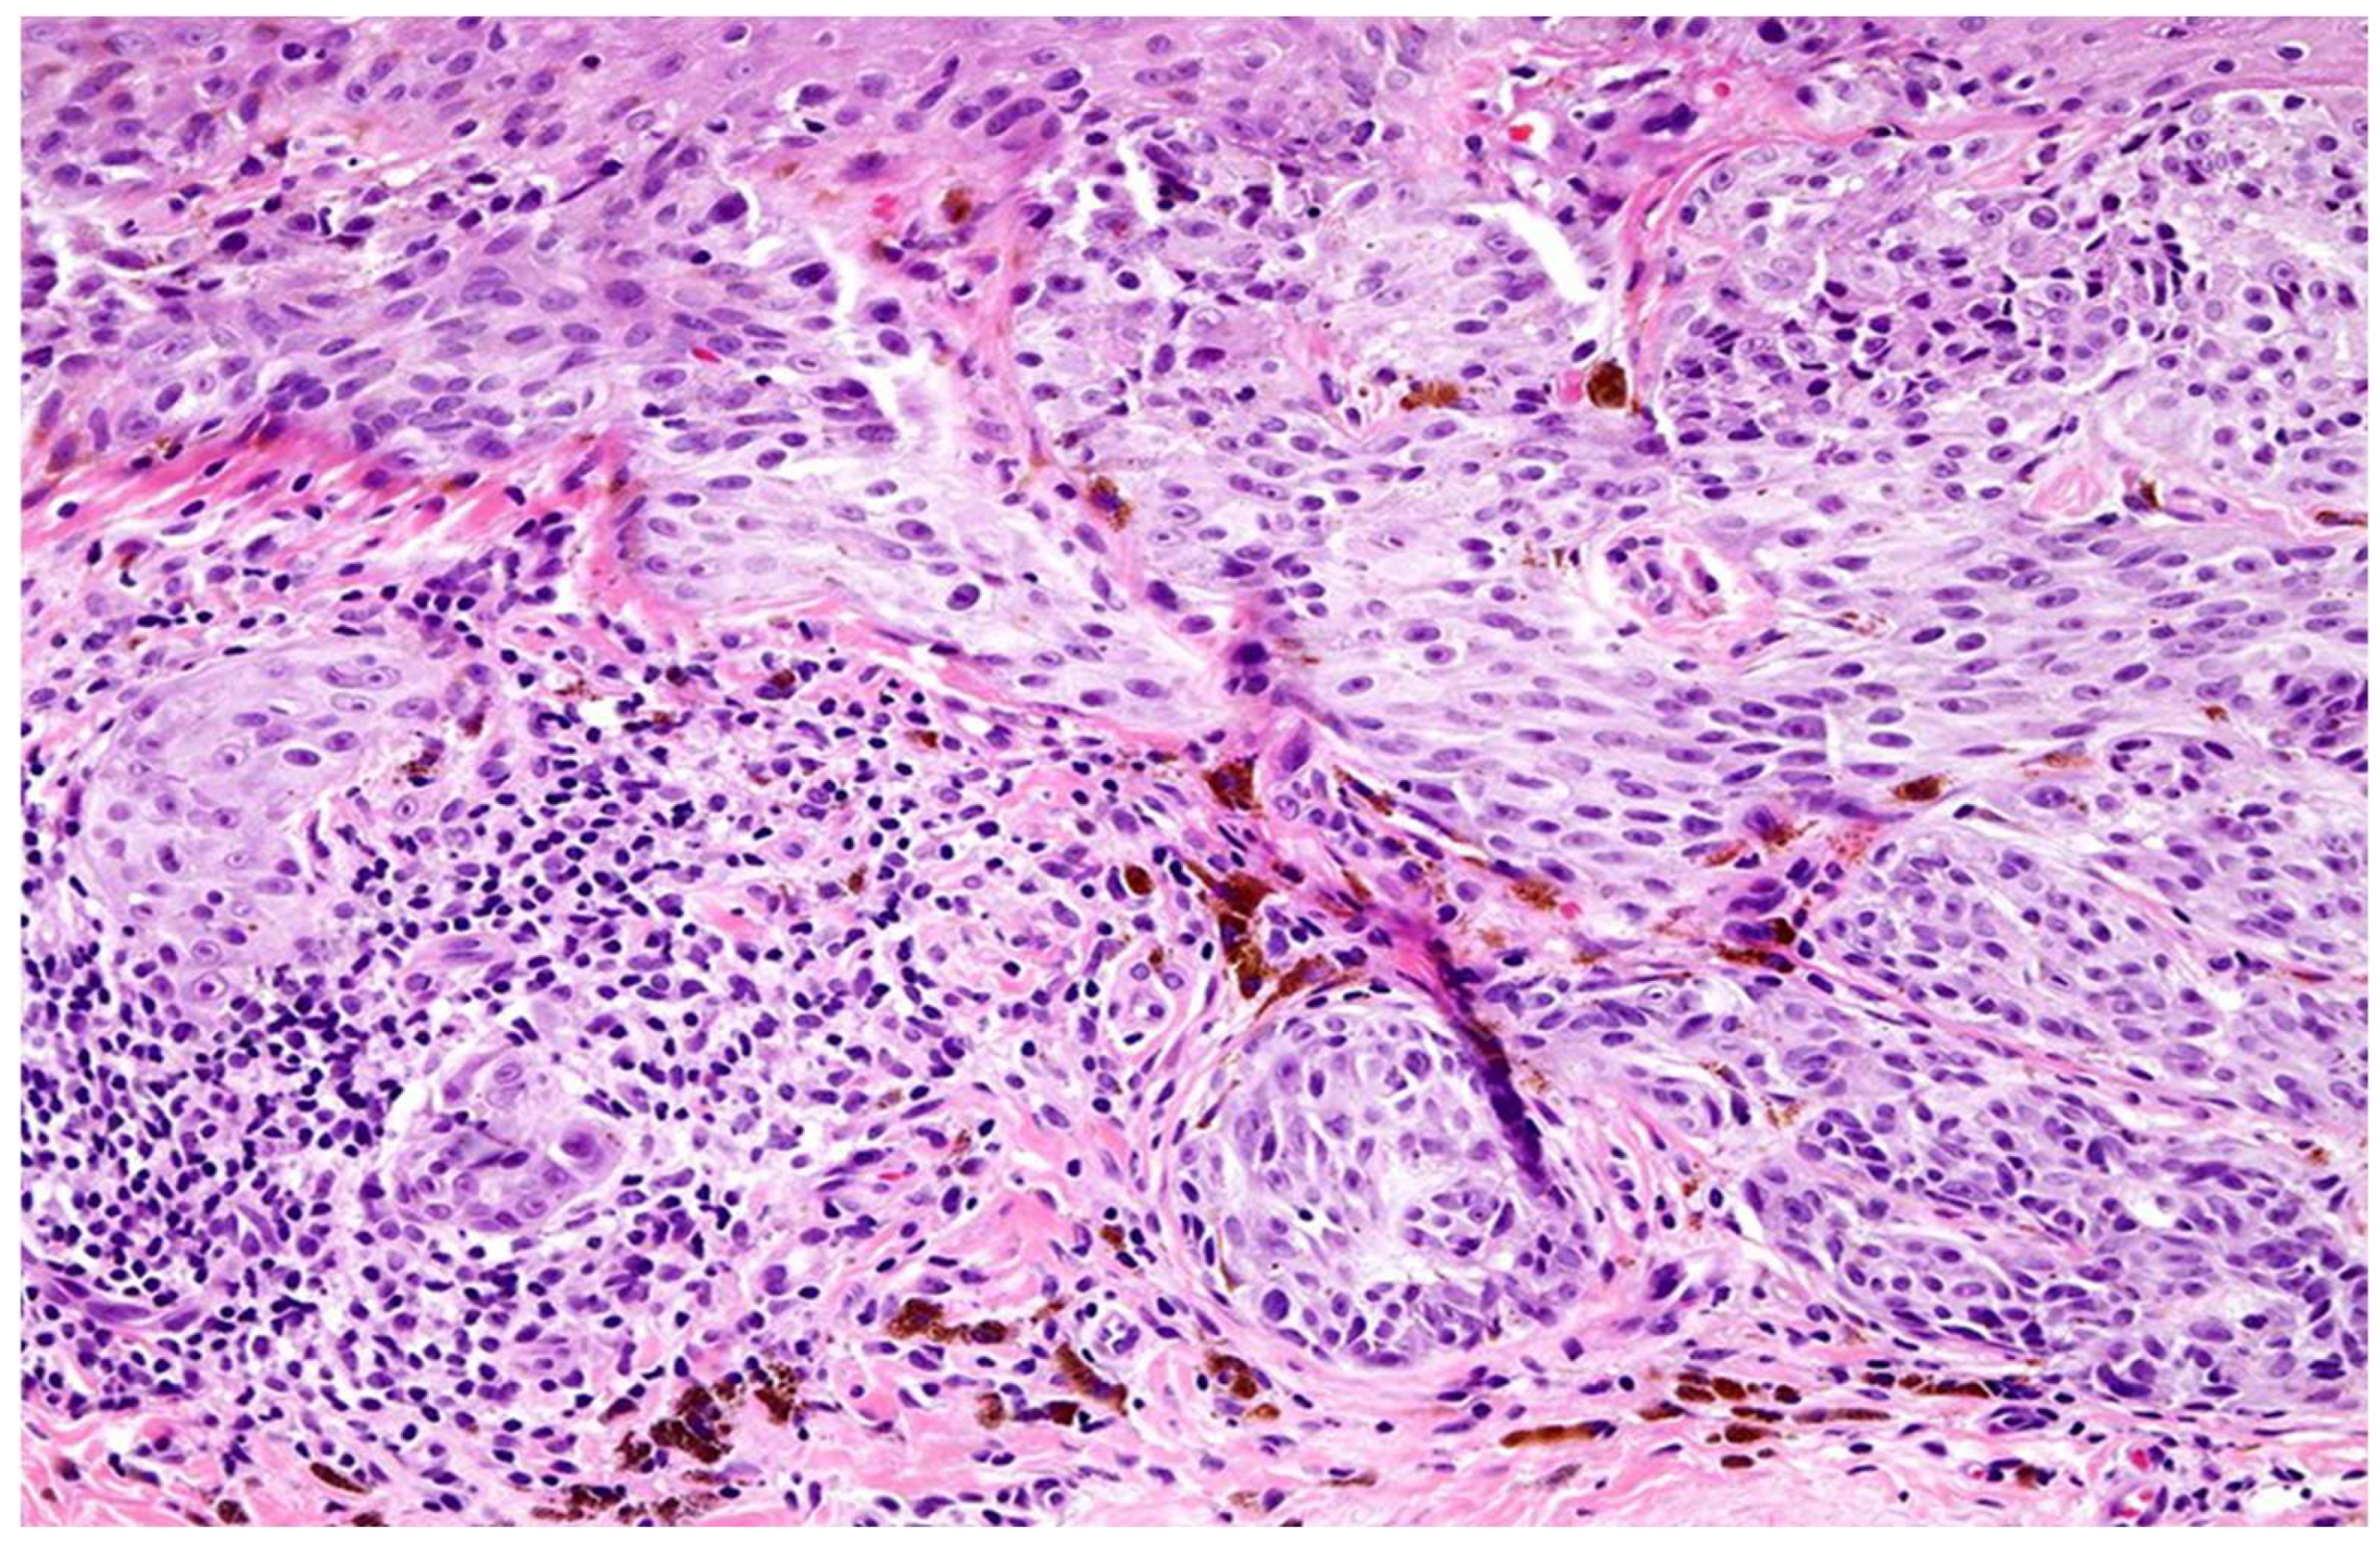

2.2.1. Histopathological Assessment of TILs

Histopathological assessment of TILs was performed on hematoxylin and eosin (H&E)-stained sections. TILs were classified according to the American Association for Cancer Research (AACR) guidelines into three distinct categories (Figure 1): brisk, non-brisk, and absent. Brisk TILs were defined as continuous, dense lymphocytic infiltrate encompassing more than 50% of the tumor perimeter and/or diffusely infiltrating tumor cell nests. Non-brisk TILs were characterized by focal or patchy infiltrates involving less than 50% of the tumor perimeter or scattered infiltration among tumor cells. Absent TILs were determined by the near-complete lack of lymphocytic infiltration within or around tumor cell nests, excluding perivascular lymphocytes or those confined to the fibrous septae.

From an initial pool of 385 archived primary cutaneous melanoma cases diagnosed between 2020 and 2024, 205 samples were selected based on predefined inclusion and exclusion criteria. Tumor-infiltrating lymphocytes (TILs) were classified into brisk (n = 65), non-brisk (n = 60), and absent (n = 80) categories by three senior pathologists according to the AACR guidelines (Figure 2). Inter-rater reliability was assessed using intra-class correlation coefficients (ICC), yielding values of 0.90 and 0.95 for brisk and absent TILs, respectively, indicating excellent agreement. Discordant cases were resolved by averaging the scores from two pathologists in agreement (Table 1).

Figure 1. Morphological patterns of tumor-infiltrating lymphocytes (TILs) according to the AACR classification tool. (A) Brisk TIL histological section showing dense peri-tumoral lymphocytic infiltration closely applied around the tumor perimeter (arrows). (B) Brisk TIL schematic representation demonstrating peri-tumoral lymphocytes with variable intra-tumoral extension. (C) Non-brisk TIL histological section showing patchy or focal lymphocytic infiltration along parts of the tumor perimeter (arrowhead). (D) Non-brisk TIL schematic representation illustrating incomplete peri-tumoral coverage by lymphocytes. (E) Absent TIL histological section and schematic showing lack of appreciable lymphocytic infiltrate at the tumor–stroma interface.

Figure 2. Melanoma tumor infiltrating lymphocytes, light micrograph. Tumor-infiltrating lymphocytes (TILs) in melanoma, showing a dense lymphocytic infiltrate within and around the melanoma, appear to correlate with a better prognosis; brisk TILs are present throughout the vertical growth phase or across. Original magnification ×20.